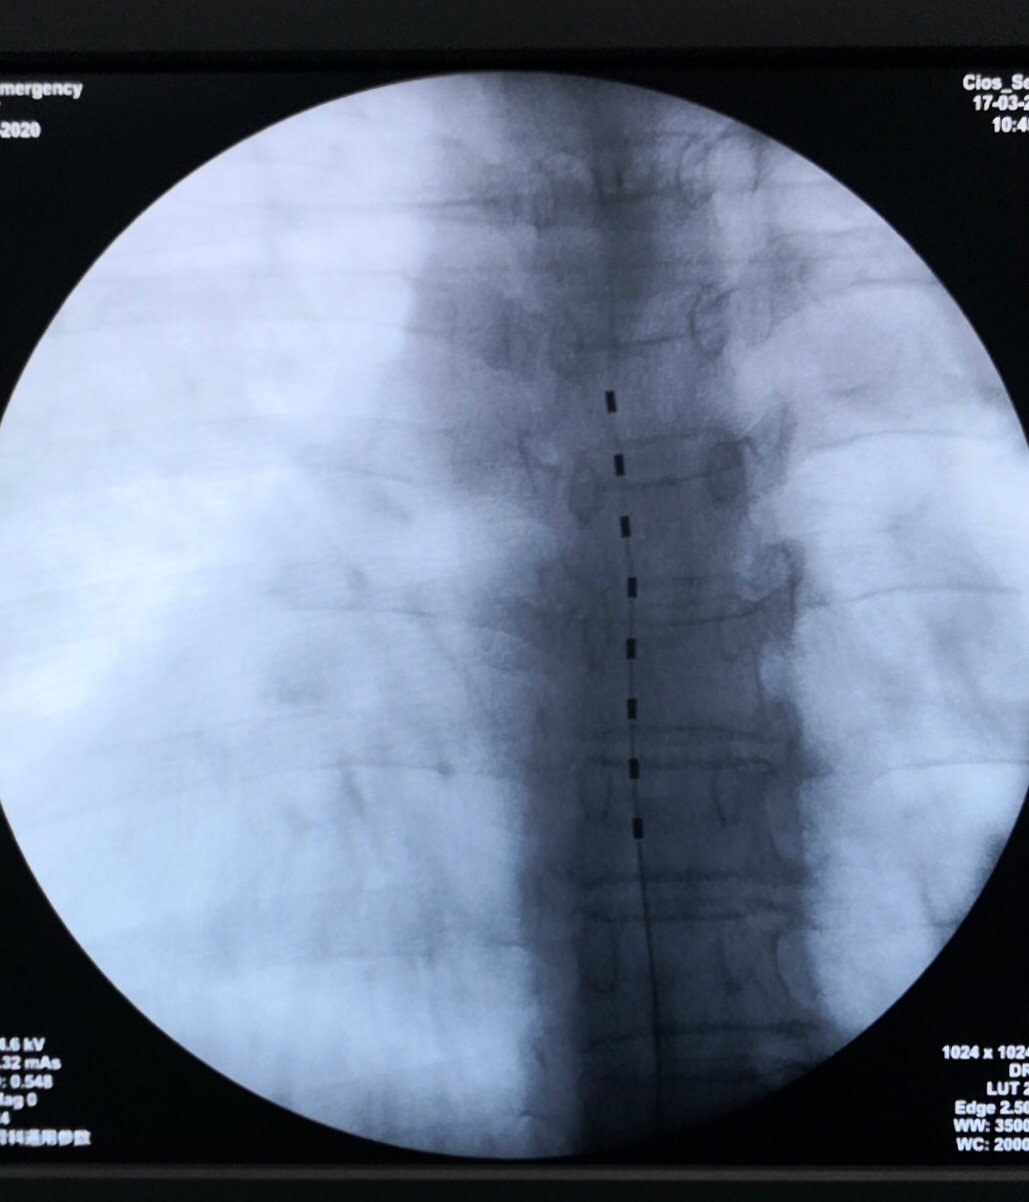

神经调控治疗包括神经阻滞、 神经根射频、 脊髓电刺激等治疗方法,简单介绍如下:1、神经阻滞疗法:通过B超引导,在神经干或神经节的周围注射消炎止痛药及医用O3,调节阻滞神经冲动传导,消除炎症。2、神经射频:通过特定的电流精准作用于神经节,抑制神经的异常放电,中止闪电痛或刀割样痛。3、脊髓或周围神经电刺激治疗:在脊髓背角或神经节干附近置入电刺激缆线,通过外置的刺激器持续作用于脊髓背角或神经节干,改善神经血供并覆盖疼痛。